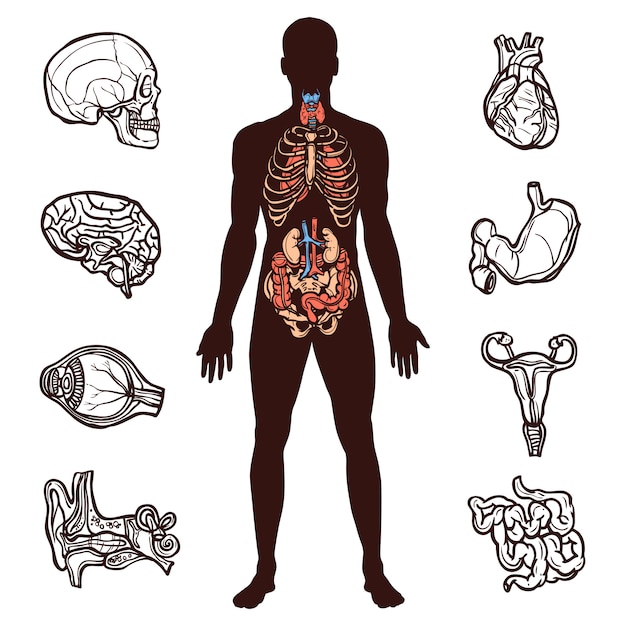

Human Anatomy Set 4378355

14/11/2025

ร่างกายมนุษย์